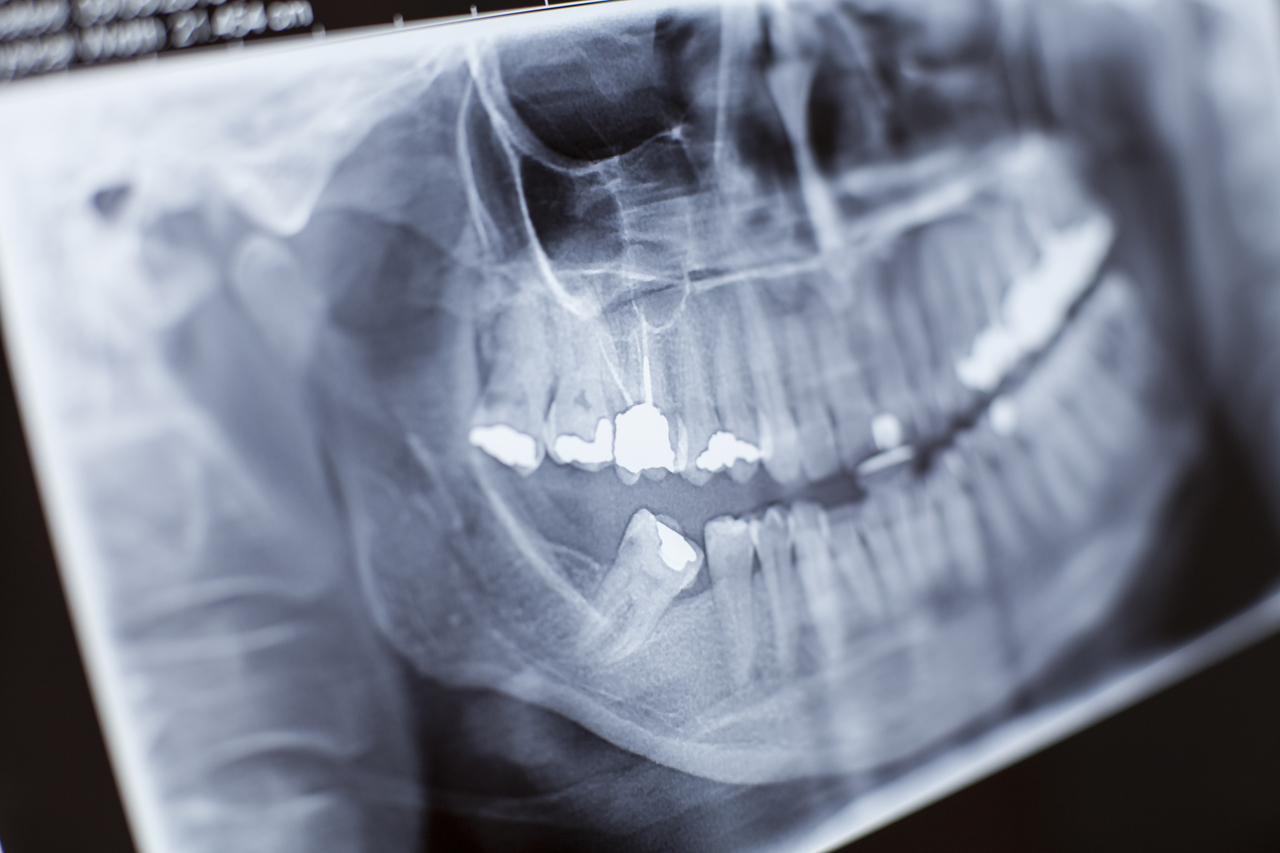

Seorang ortodontis akan menilai gigi dan gigitan anda untuk memutuskan jika braces gigi hanya untuk gigi atas adalah pilihan yang tepat. Doktor gigi kami akan menggunakan alat X-ray untuk mendapatkan gambaran jelas tentang bagaimana gigi dan rahang anda berfungsi bersama.